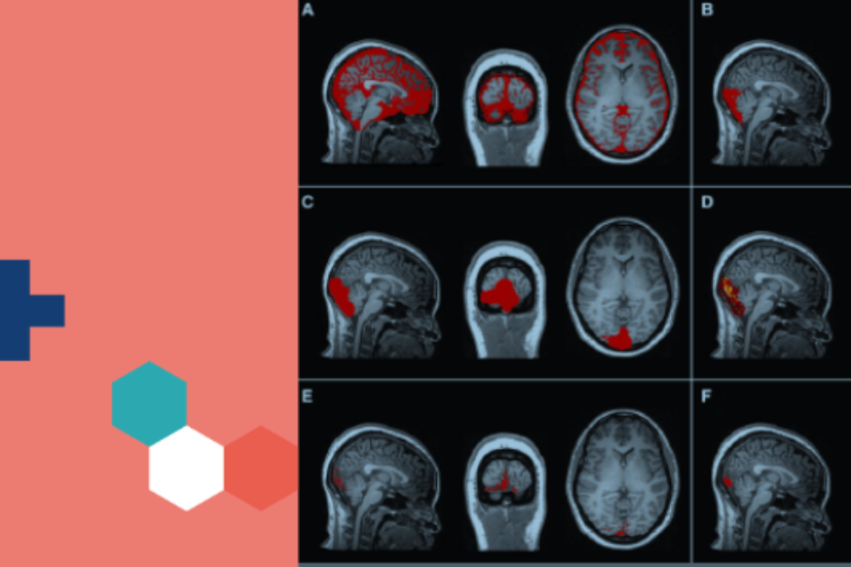

Federico Turkheimer is Professor in Neuroimaging (Analysis & Statistics) and leads the King’s Human and Synthetic Minds Institute at King’s College London. He uses Positron Emission Tomography (PET) and Magnetic Resonance Imaging (MRI) to model brain physiology in health and disease.

Presently his work is focused on brain immunity and its relationship with the peripheral immune system and glymphatic function, the clearance system of the brain.